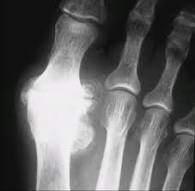

Ketika gangguan berlangsung, aktivitas inflamasi akan menyebabkan erosi dan kehancuran sendi yang akan mengganggu mereka di berbagai gerakan dan mengakibatkan beberapa kelainan bentuk.

Jari-jari dan tulang-tulang akan menyimpang ke luar dan ke arah jari yang kecil dan membuat bentuk yang tidak wajar.

Jenis kelainan bentuk pada penderita rheumatoid arthritis ini diantaranya adalah kelainan Boutonnière, kelainan bentuk leher angsa, dan kelainan "Z-thumb".

Arthritis pada persendian di tangan seperti arthritis simetris, nodul subkutan di tempat-tempat tertentu, faktor rheumatoid ada di tingkat ke-95 dan perubahan radiologis yang berasal dari erosi pada persendian merupakan bagian dari kriteria yang harus dipenuhi untuk membuat sebuah diagnosa.